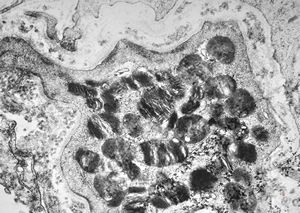

M, 62y. | mitosis … angiomatous tumor, v.s. Kaposi sarcoma

M, 62y. | angiomatous tumor, v.s. Kaposi sarcoma

M, 62y. | Weibel-Palade body - angiomatous tumor, v.s. Kaposi sarcoma